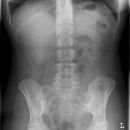

Abdomen liegend a.-p.

Qualitätskriterien

Untere Bildbegrenzung: Symphysenunterrand, obere Bildbegrenzung: beide Zwerchfell. Wirbelsäule in der Mitte. Die Belichtung sollte es erlauben, den Leberunterrand, die Nierenkonturen, die Psoasrandkonturen sowie die Bauchwand und Fettlinien zu erkennen.